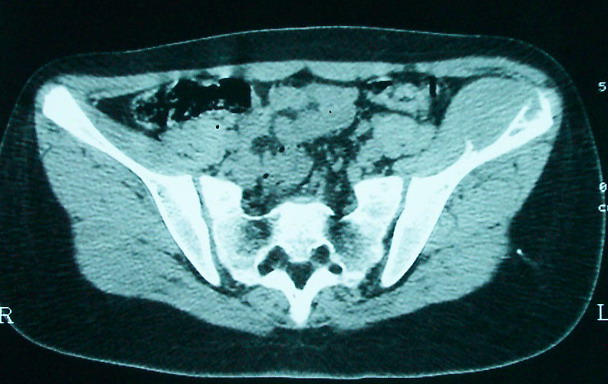

女 13岁 4月前有臀部肌肉注射史 3月前发热 最高体温38.5 2月前出现左髂骨疼痛 不剧烈能忍受 发热时高时低 按感冒治疗无好转 近日左髂骨疼痛加重 一星期前wbc 12.2 今日wbc9.5

左侧髂骨溶骨性骨质破坏,骨皮质侵蚀,灶周可见软组织肿块,支持考虑骨肉瘤可能性大。

髓腔起源,弥漫性溶骨性骨质破坏并软组织肿块,膨胀不明显,无显著钙化及瘤骨,有骨膜反应,结合年龄考虑恶性,尤文氏肉瘤可能性大。

鉴别:尤文氏肉瘤>毛细血管扩张型骨肉瘤>骨原发淋巴瘤>朗格罕氏细胞增生症>软黏纤>慢性骨髓炎>tb。